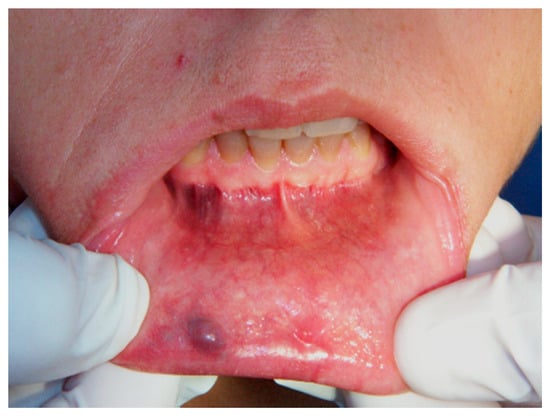

Aesthetic Treatment Outcomes of Capillary Hemangioma, Venous Lake, and Venous Malformation of the Lip Using Different Surgical Procedures and Laser Wavelengths (Nd:YAG, Er,Cr:YSGG, CO2, and Diode 980 nm)

2.2. Participants